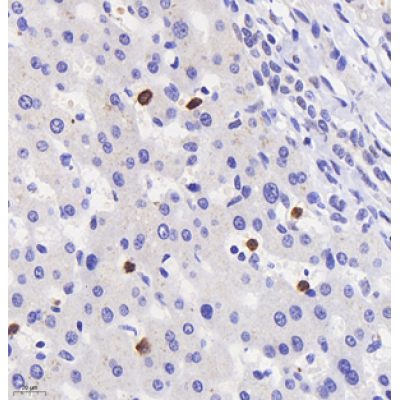

| IHC analysis of mpo (GB11224). Sample: Human liver (Paraffin), 4% PFA (G1101) 12-24h. Antigen retrieval: Citrate buffer (pH 6.0) (G1201),98°C,20 min. Blocking buffer: 3% BSA in PBS (GC305010), RT, 30min. Primary antibody: 1: 1000, 4°C overnight. Secondary antibody: HRP Goat Anti-Rabbit lgG (GB23303), 1: 200 RT 1h. |

| IHC analysis of mpo (GB11224). Sample: Mouse liver+lps (Paraffin), 4% PFA (G1101) 12-24h. Antigen retrieval: Citrate buffer (pH 6.0) (G1201),98°C,20 min. Blocking buffer: 3% BSA in PBS (GC305010), RT, 30min. Primary antibody: 1: 1000, 4°C overnight. Secondary antibody: HRP Goat Anti-Rabbit lgG (GB23303), 1: 200 RT 1h. |

| IHC analysis of MPO (GB11224). Sample: Mouse bone (Paraffin), 4% PFA (G1101) 12-24h. Antigen retrieval: Citrate buffer (pH 6.0) (G1201),98°C,20 min. Blocking buffer: 3% BSA in PBS (GC305010), RT, 30min. Primary antibody: 1: 800, 4°C overnight. Secondary antibody: HRP Goat Anti-Rabbit lgG (GB23303), 1: 200 RT 1h. |

| IHC analysis of mpo (GB11224). Sample: Rat liver+lps (Paraffin), 4% PFA (G1101) 12-24h. Antigen retrieval: Citrate buffer (pH 6.0) (G1201),98°C,20 min. Blocking buffer: 3% BSA in PBS (GC305010), RT, 30min. Primary antibody: 1: 1800, 4°C overnight. Secondary antibody: HRP Goat Anti-Rabbit lgG (GB23303), 1: 200 RT 1h. |

| IHC analysis of mpo (GB11224). Sample: Rat lung+lps (Paraffin), 4% PFA (G1101) 12-24h. Antigen retrieval: Citrate buffer (pH 6.0) (G1201),98°C,20 min. Blocking buffer: 3% BSA in PBS (GC305010), RT, 30min. Primary antibody: 1: 1200, 4°C overnight. Secondary antibody: HRP Goat Anti-Rabbit lgG (GB23303), 1: 200 RT 1h. |

| IHC analysis of mpo (GB11224). Sample: Rat lung+lps (Paraffin), 4% PFA (G1101) 12-24h. Antigen retrieval: Citrate buffer (pH 6.0) (G1201),98°C,20 min. Blocking buffer: 3% BSA in PBS (GC305010), RT, 30min. Primary antibody: 1: 1800, 4°C overnight. Secondary antibody: HRP Goat Anti-Rabbit lgG (GB23303), 1: 200 RT 1h. |

| IHC analysis of MPO (GB11224). Sample: Rat spleen (Paraffin), 4% PFA (G1101) 12-24h. Antigen retrieval: Citrate buffer (pH 6.0) (G1201),98°C,20 min. Blocking buffer: 3% BSA in PBS (GC305010), RT, 30min. Primary antibody: 1: 3000, 4°C overnight. Secondary antibody: HRP Goat Anti-Rabbit lgG (GB23303), 1: 200 RT 1h. |